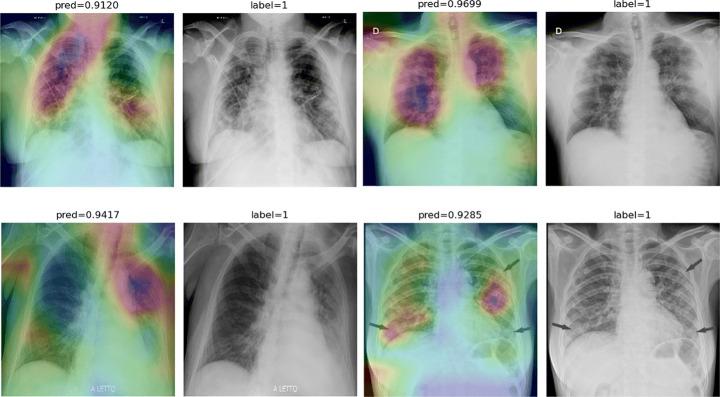

One of the primary clinical observations for screening the novel coronavirus is capturing a chest x-ray image. In most patients, a chest x-ray contains abnormalities, such as consolidation, resulting from COVID-19 viral pneumonia. In this study, research is conducted on efficiently detecting imaging features of this type of pneumonia using deep convolutional neural networks in a large dataset. It is demonstrated that simple models, alongside the majority of pretrained networks in the literature, focus on irrelevant features for decision-making. In this paper, numerous chest x-ray images from several sources are collected, and one of the largest publicly accessible datasets is prepared. Finally, using the transfer learning paradigm, the well-known CheXNet model is utilized to develop COVID-CXNet. This powerful model is capable of detecting the novel coronavirus pneumonia based on relevant and meaningful features with precise localization. COVID-CXNet is a step towards a fully automated and robust COVID-19 detection system.

筛查新型冠状病毒的主要临床观察方法之一是拍摄胸部X光图像。在大多数患者中,胸部X光显示出由COVID-19病毒性肺炎引起的异常,如实变。在本研究中,我们利用深度卷积神经网络在一个大型数据集中对这种类型肺炎的成像特征进行高效检测。结果表明,简单模型以及文献中的大多数预训练网络都关注于与决策无关的特征。本文收集了来自多个来源的大量胸部X光图像,并准备了一个最大的公开可用数据集。最后,使用迁移学习范式,利用著名的CheXNet模型开发了COVID-CXNet。这个强大的模型能够基于相关且有意义的特征精确地定位检测新型冠状病毒肺炎。COVID-CXNet朝着全自动且强大的COVID-19检测系统迈出了一步。